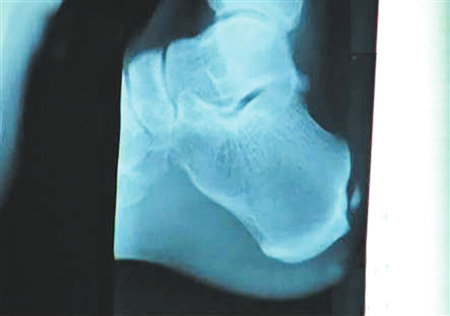

組圖:劉翔跟腱手術全過程揭秘

手術要取出的鈣化物就在這里。 圖片來源:華西都市報

北京時間12月6日凌晨,備受關注的中國飛人劉翔在休斯頓赫曼紀念醫院的跟腱手術成功結束。